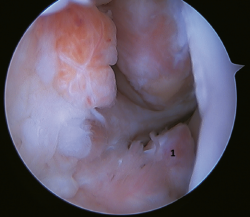

The main indication for this repair is rupture of the upper fascicle of the ATFL from its fibular insertion, with good tissue quality of the remaining ligament (Figure 3).

The technique can be performed through a single modified anterolateral portal or using a third accessory portal. The use of a single portal reduces the risk of injury to the intermediate dorsal cutaneous branch of the superficial peroneal nerve(37). Although there is no difference between the use of one or two implants, the use of two implants implies a larger contact surface(38,39) and improves patient incorporation to sports activities(40,41,42,43,44).

Another aspect to be considered is the angle of implant placement, due to possible complications related to drilling of the tunnels in the fibula. The best angle is between 30º and60°. An angle of30° is associated with an increased risk of peroneal tendon injuries, and an angle of60° increases the risk of fibular cortical fracture, with the recommended angle being about45°(43).

Vega(42) advocated the use of synthetic augmentation employing high-strength sutures, with the publishing of excellent results. Ulku(44) reported results comparable to the open Broström-Gould procedure with this technique, it being described as an arthroscopically safe procedure. In 2021, Lan(45) carried out a systematic review of the different augmentation techniques, concluding that the best results are obtained when previous repair of the ATFL remnant has been performed either by an open or arthroscopic procedure; he did not recommend the use of isolated augmentation, due to the poorer results obtained. In 2023, Mortada(38) published excellent results with this technique, using two implants and a single modified portal in a series of 100 patients, with statistically significant improvement on the AOFAS and Karlsson scales.

Figure 3. A: identification of the fibular insertion of the ATFL (*) with excellent quality of the tissue remnant; B: technique with two knotless implants and using a modified single anterolateral portal; C: final result. P: fibula; T1: talofibular tunnel; T2: calcaneofibular tunnel.